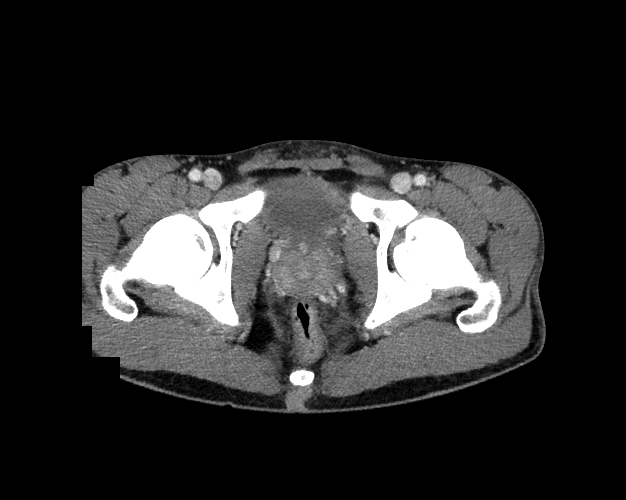

Pelvis

Covers pelvic MRI anatomy.